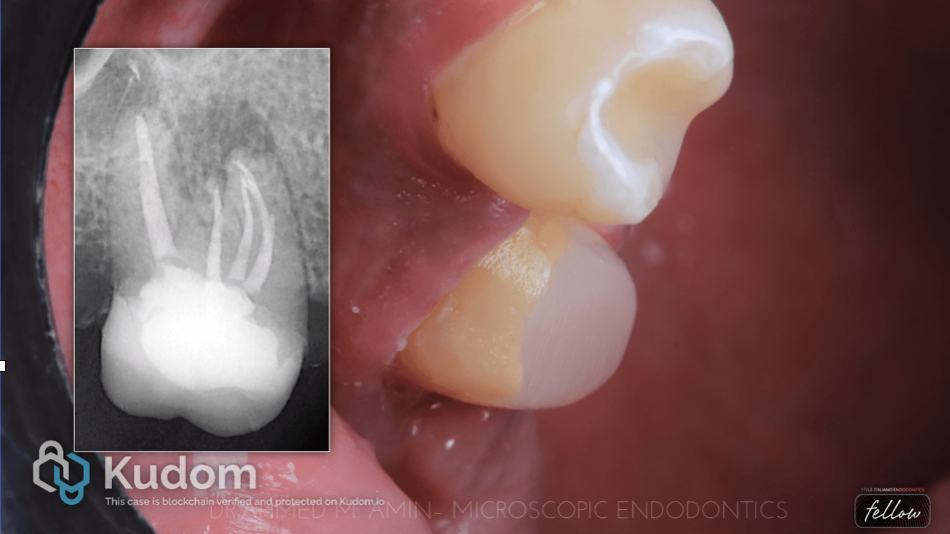

Fig. 2

We decided to do a gingivectomy on the distal side, remove all the caries, and remove the metal post to be able to assess the restorability of the tooth.

But first we need to isolate the tooth as In endodontics, the rubber dam is not just an "option"; it is the standard of care. It serves as the primary barrier between a successful clinical outcome and a potential failure due to contamination or accident.